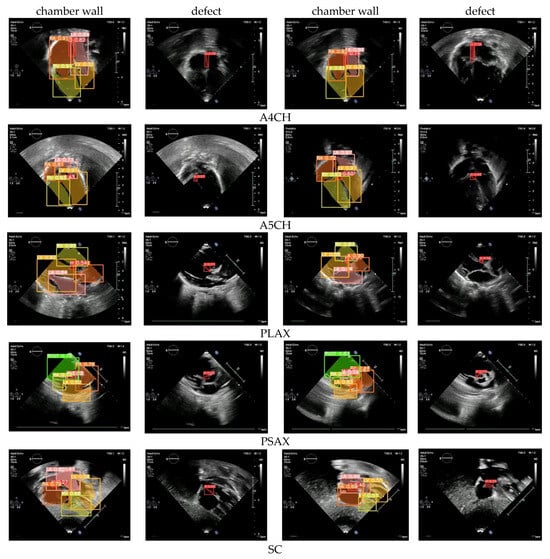

3.4. Defect Detection

Defect detection is the essential process of identifying and diagnosing anomalies within the heart. The timely detection of these anomalies is critical for initiating appropriate treatment and effectively managing CSD conditions, which can profoundly influence a child’s health and overall well-being. Based on the normal–abnormal and view classification results, we employed Yolov8l to perform defect detection. The mAP was utilized to assess the performance of both the validation and unseen data. We utilized the five standard cardiac views to ensure thorough results: A4CH, A5CH, PLAX, PSAX, and SC. These views play a pivotal role in precisely evaluating the cardiac chamber wall classes, including RA, RV, LA, LV, and identifying any septal defects (H) within the heart (Figure 8).

Chamber wall detection (LA, RA, LV, RV) across the five views yielded satisfactory results, both in terms of the validation and unseen data, with the mAP value exceeding 90%. However, in the defect detection or hole (H) detection, the mAP average value dropped below 85%. The A4CH and SC views successfully detect with a mAP of over 80%, whereas A5CH, PLAX, and PSAX only achieve mAP values below 65% for the validation data and below 60% for the unseen data. It can be observed that achieving accurate detection in both the A4CH and A5CH views poses significant challenges due to their similarity. The main point of differentiation in the A5CH view is the presence of the aorta in the middle of the chamber wall. As a result, errors are quite common during both the validation and unseen test phases. The parasternal view (PLAX and PSAX) provides a longitudinal slice of the heart, which may not offer a comprehensive view of all the cardiac structures. Certain defects, especially those located in less visible areas or those requiring a different angle of approach, may not be easily detected. However, achieving a mAP value greater than 50%, the model demonstrated the effective detection of cardiac defects.

Based on the test results obtained using the proposed framework, the model demonstrates a highly satisfactory performance in defect detection. Utilizing five views, we measured the mAP bounding box (BBox) and mAP pixel-wise binary mask (Mask) (Table 3). The mAP BBox quantifies the accuracy of object detection, while the mAP Mask evaluates the effectiveness of instance segmentation models. Both metrics are crucial for assessing the performance of the proposed Yolov8l. The results reveal that the achieved mAP ranges from 60% to 89% for the validation data and from 50% to 80% when tested with the unseen data. These findings indicate that the defect detection performance exceeds the baseline mAP threshold of 50%, indicating increased confidence levels in the detection outcomes.

Detecting defects can be challenging due to the heart being a complex three-dimensional organ with intricate structures. Some defects may be subtle or located in areas where they are obscured by other cardiac structures, making them difficult to identify from a single imaging plane. Our framework uses a combination of five views to make a CSD decision. A visualization of our results to show an object detection scheme on the chamber wall and hole is shown in Figure 10. There are walls that separate the chambers, and each chamber has its own walls. The septum is the primary wall that divides the cardiac into left and right sides. There is the interatrial septum between the atria and the interventricular septum between the ventricles. LA, LV, RA, RV are objects that must be detected on the chamber wall, so as to assist in determining the position of defects or holes. By identifying the position of defects or holes in these walls, it helps in diagnosing the type of CSD.

The value obtained in each image represents the confidence level of the detection results. For the purposes of this study, a confidence value exceeding 0.5 can be deemed indicative of a reliable decision. It can be observed that all the confidence values are above the baseline value, meaning that the proposed Yolov8l model is capable of exhibiting a reliable detection performance for defects in the cardiac septum.

Figure 8. The CSD detection performance using our framework on five standard views.

Figure 10. The sample of CSD detection images in five views.